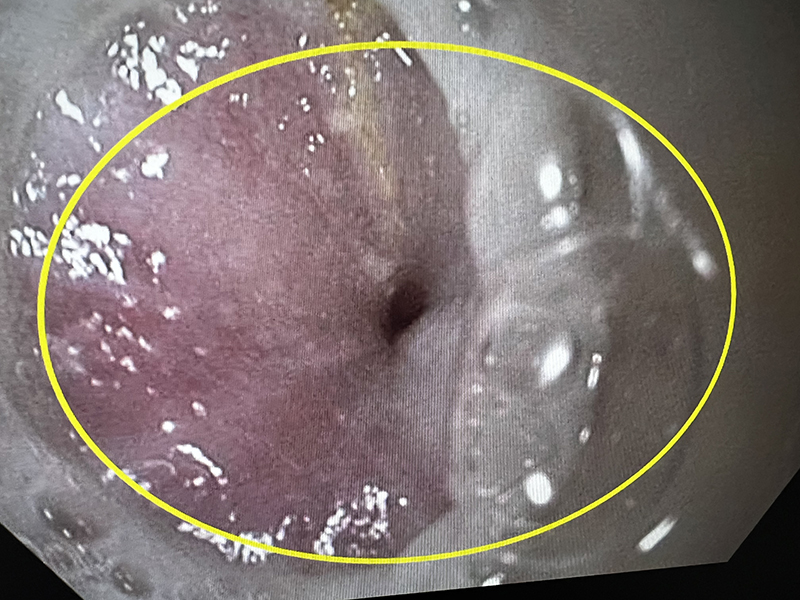

The esophago-gastric junction before myotomy

With the E-POEM secondary to achalasia, the EGJ was spastic and had much fibrosis due to disease